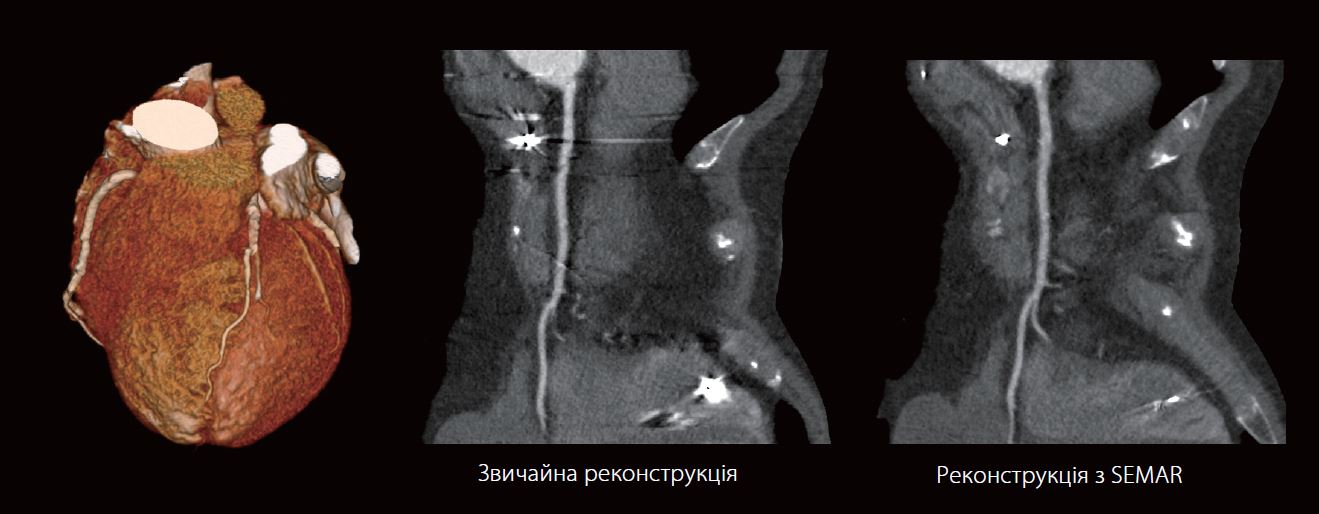

69-річний чоловік з кардіостимулятором і протезом аортального клапана звернувся з болем у грудях. Для виключення ішемічної хвороби серця було запропоновано коронарографію.

На звичайній реконструкції верхній відділ правої коронарної артерії частково закритий артефактами. На реконструкції з SEMAR Артефакти, спричинені металевими електродами кардіостимулятора, більше не видно. Також, можна побачити, що в судині не має стенозу, чого не можна було б стверджувати на звичайній реконструкції.

ЕКГ-синхронізована SEMAR (Single Energy Metal Artifact Reduction) долає одну з невирішених проблем у зчитуванні коронарних CTA досліджень у пацієнтів з імплантованими серцевими пристроями, такими як кардіостимулятори та дефібрилятори.

Використовуючи протокол сканування зі звичайною дозою та унікальний процес реконструкції, SEMAR може зменшити металеві артефакти, які могли б заважати візуалізації найближчих коронарних артерій.